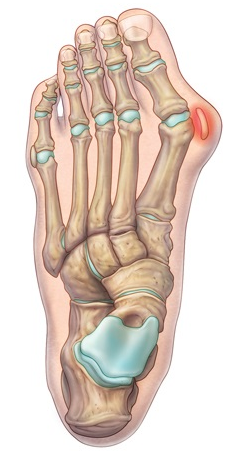

• Na avaliação radiográfica em AP com carga, quais os principais ângulos a serem traçados?

A

• Ângulo de valgismo do hálux (metatarsofalângico)

• Ângulo intermetatarsal

• Ângulo de valgismo interfalângico do hálux

• Ângulo articular metatarsal distal (AAMD)

• Na radiografia em AP com carga, como é traçado o ângulo intermetatarsal?

• Ângulo entre o eixo longo do 1° e do 2° raio

• Normal → até 9°

• Leve → 9° a 12°

• Moderado → 13° a 15°

• Grave → > 16°

17

Q

Hálux valgo

• Na radiografia em AP com carga, como é traçado o ângulo de valgismo do hálux (metatarsofalângico)?

• Ângulo entre o eixo longo do 1° mtt e o eixo longo da falange proximal

• Normal → até 15°

• Leve → < 25°

• Moderado → 25° a 40°

• Grave → > 40°

18

• Na radiografia em AP com carga, como é traçado o ângulo de valgismo interfalângico do hálux?

• Ângulo entre o eixo longo da falange proximal e o eixo longo da falange distal

• Normal → até 10°

19

• Na radiografia em AP com carga, como é traçado o ângulo articular metatarsal distal (AAMD)?

• Traça-se uma linha unindo os dois pontos mais largos da superfície articular do 1° mtt e outra linha perpendicular a esta

• Depois, traça-se uma linha no eixo longo do 1° mtt

• O ângulo entre as duas maiores retas → até 15°